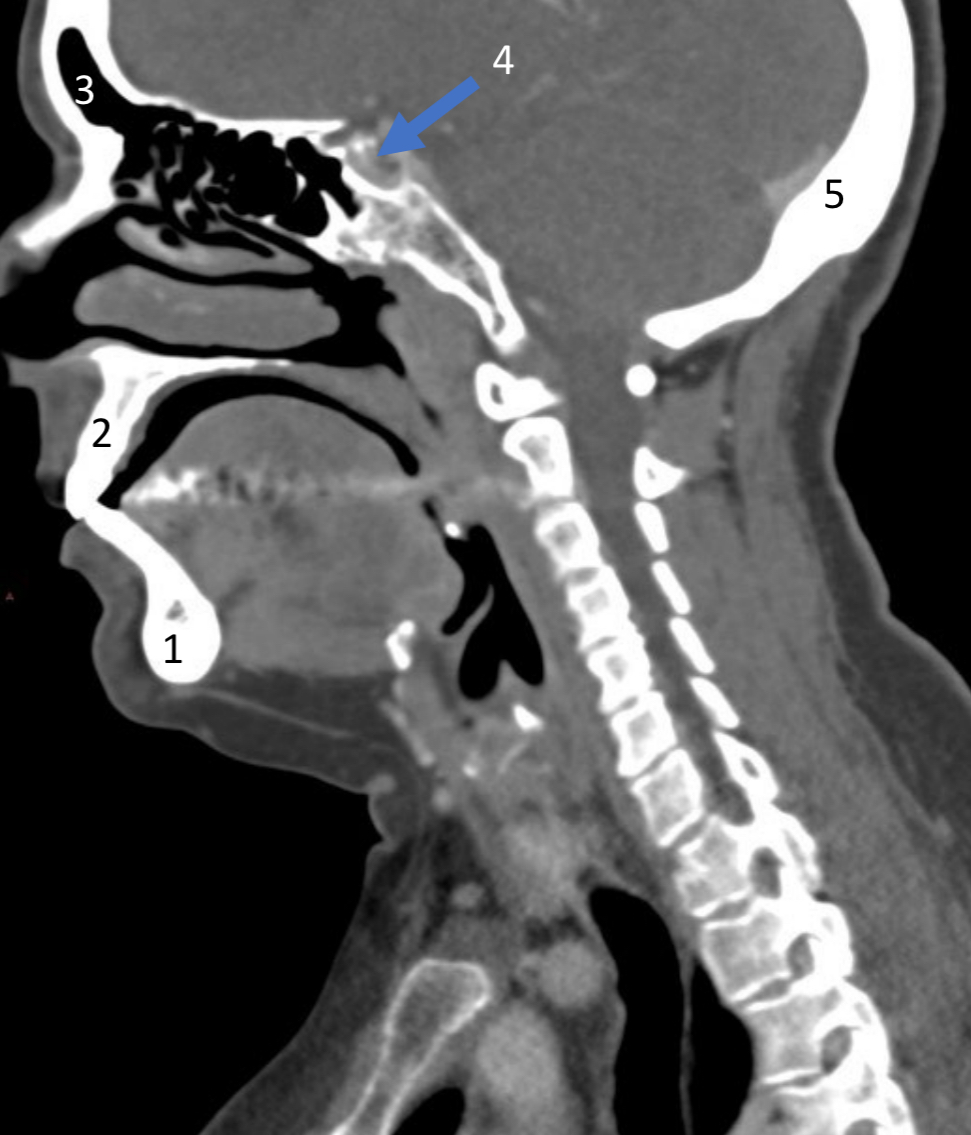

Mandible

ID bone

Maxilla

ID bone

Frontal sinus

ID structure

Pituitary fossa

ID structure

Occipital

ID bone

Lambdoid suture

ID structure

Frontal sinus

ID structure

Orbital margin

Orbit

Maxillary sinus

ID structure

Mandibular condyle

ID structure

Inferior nasal concha

ID structure

Hard palate

ID strucutre

Gonial angle

ID strucutre

Petrous ridge

ID structure

Groove of middle meningeal a.

ID structure

Roof of orbit

ID structure

Frontal sinus

ID structure

Pituitary fossa

ID structure

Petrous ridge

ID structure

Sphenoid sinus

ID structure

Hard palate

ID structure

Mastoid air cells

ID structure

Zygomatic arch

ID structure

Mandibular condyle

ID structure

External auditory meatus

ID structure

Mastoid air cells

ID structure

Foramen magnum

ID structure

Foramen ovale

ID structure

Foramen spinosum

ID structure